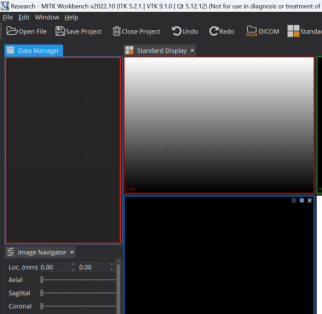

Step 2: 导入图像。即手动将亟待标注的”.nii.gz”文件拖动到下图区域

Step 3: 调节窗宽窗位。有两种方式,手动设置及滑动调节。如果标注肝肿瘤,我手动将窗宽窗位调节到[40-400]